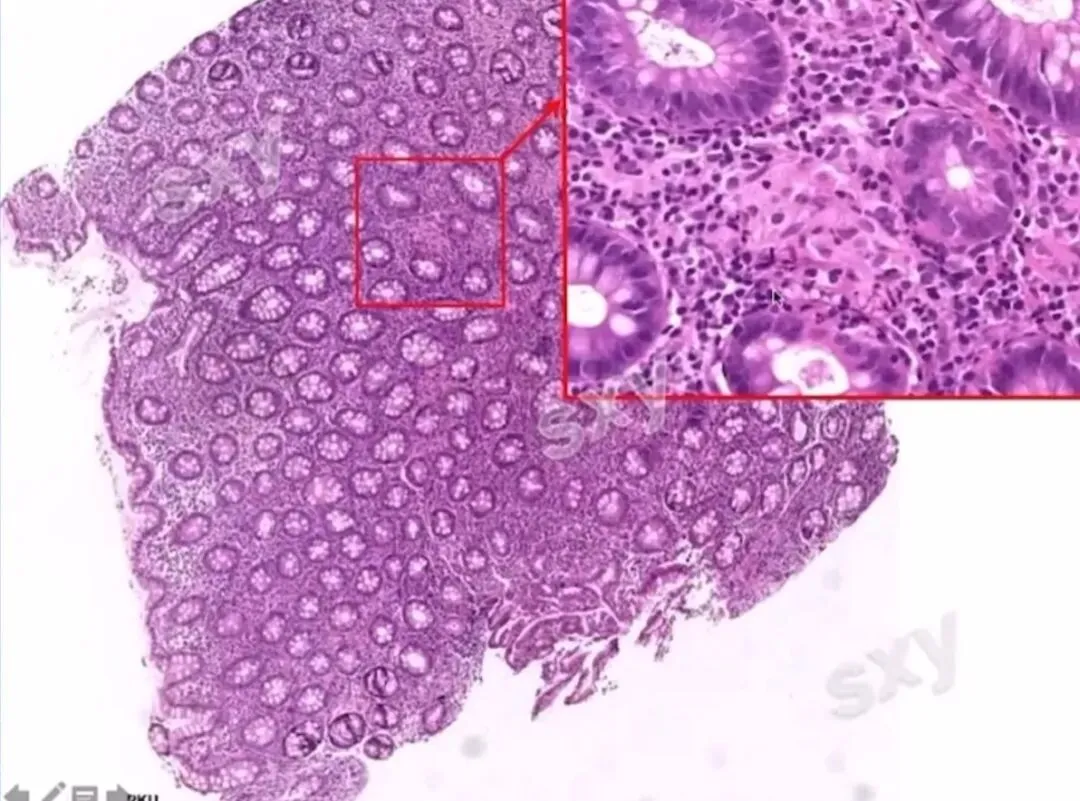

>课件分享:炎症性肠病的病理诊断

课件分享:炎症性肠病的病理诊断